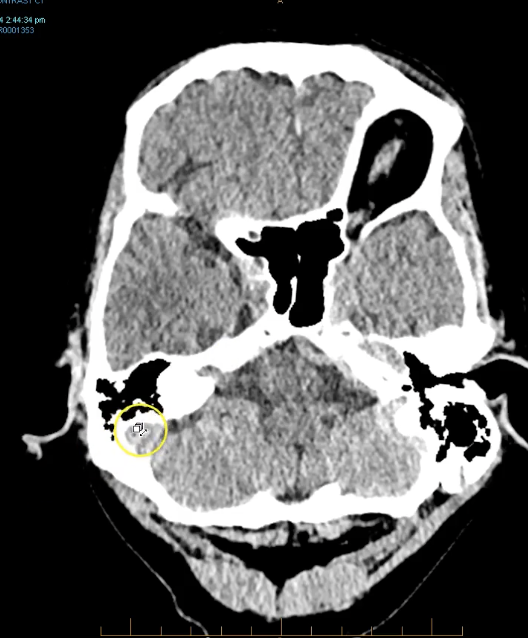

term image

crescent shaped collection wit various densities in it indicating chronic haematoma but also acute haematoma.